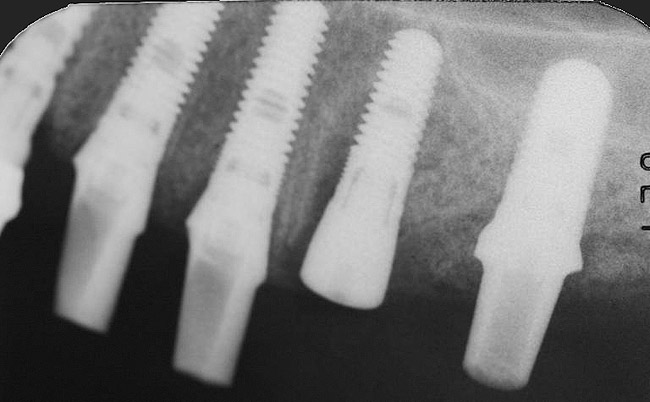

Increasing the number of implants can compensate for decreasing weakness of bone.27 A greater number of implants will provide increased functional loading area and reduced stress on bone. For example, in D2 bone, a pontic may be placed between two implants; whereas, in D3 bone, it may be advantageous to place one implant per tooth (Figure 7).28 In less dense bone, cantilevers should be avoided, and if contemplated, consideration should be given to increasing the number and size of the implants.